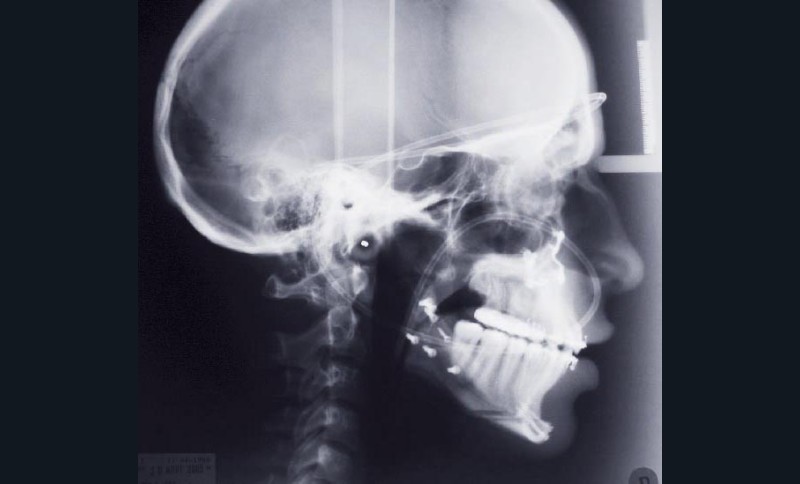

Les mouvements de décompensations sagittales et transversales sont réalisés à l’aide des tractions inter-arcades. La réévaluation céphalométrique et l’analyse des moulages confirment l’indication d’une chirurgie maxillaire de propulsion et d’une chirurgie mandibulaire par clivage bilatéral des branches montantes pour un recul mandibulaire modéré accompagné d’une génioplastie bidimensionnelle élargie qui rappelle la technique de Chin Wing.

Les résultats esthétiques et occlusaux satisfont amplement le patient qui revient pour un contrôle à long terme 10 ans après l’intervention montrant la stabilité des résultats.